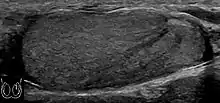

Fig. 7. Lymphoma. Lymphoma in a 61-year-old man. Longitudinal sonography shows an irregular hypoechoic lesion occupied nearly the whole testis.

Fig. 8. Primary Lymphoma. Longitudinal sonography of a 64-year-old man shows a lymphoma mimicking a germ cell tumor.

Clinically lymphoma can manifest in one of three ways: as the primary site of involvement, or as a secondary tumor such as the initial manifestation of clinically occult disease or recurrent disease. Although lymphomas constitute 5% of testicular tumors and are almost exclusively diffuse non-Hodgkin B-cell tumors, only less than 1% of non-Hodgkin lymphomas involve the testis.

Patients with testicular lymphoma are usually old aged around 60 years of age, present with painless testicular enlargement and less commonly with other systemic symptoms such as weight loss, anorexia, fever and weakness. Bilateral testicle involvements are common and occur in 8.5% to 18% of cases. At sonography, most lymphomas are homogeneous and diffusely replace the testis [Fig. 7]. However focal hypoechoic lesions can occur, hemorrhage and necrosis are rare. At times, the sonographic appearance of lymphoma is indistinguishable from that of the germ cell tumors [Fig. 8], then the patient's age at presentation, symptoms, and medical history, as well as multiplicity and bilaterality of the lesions, are all important factors in making the appropriate diagnosis.